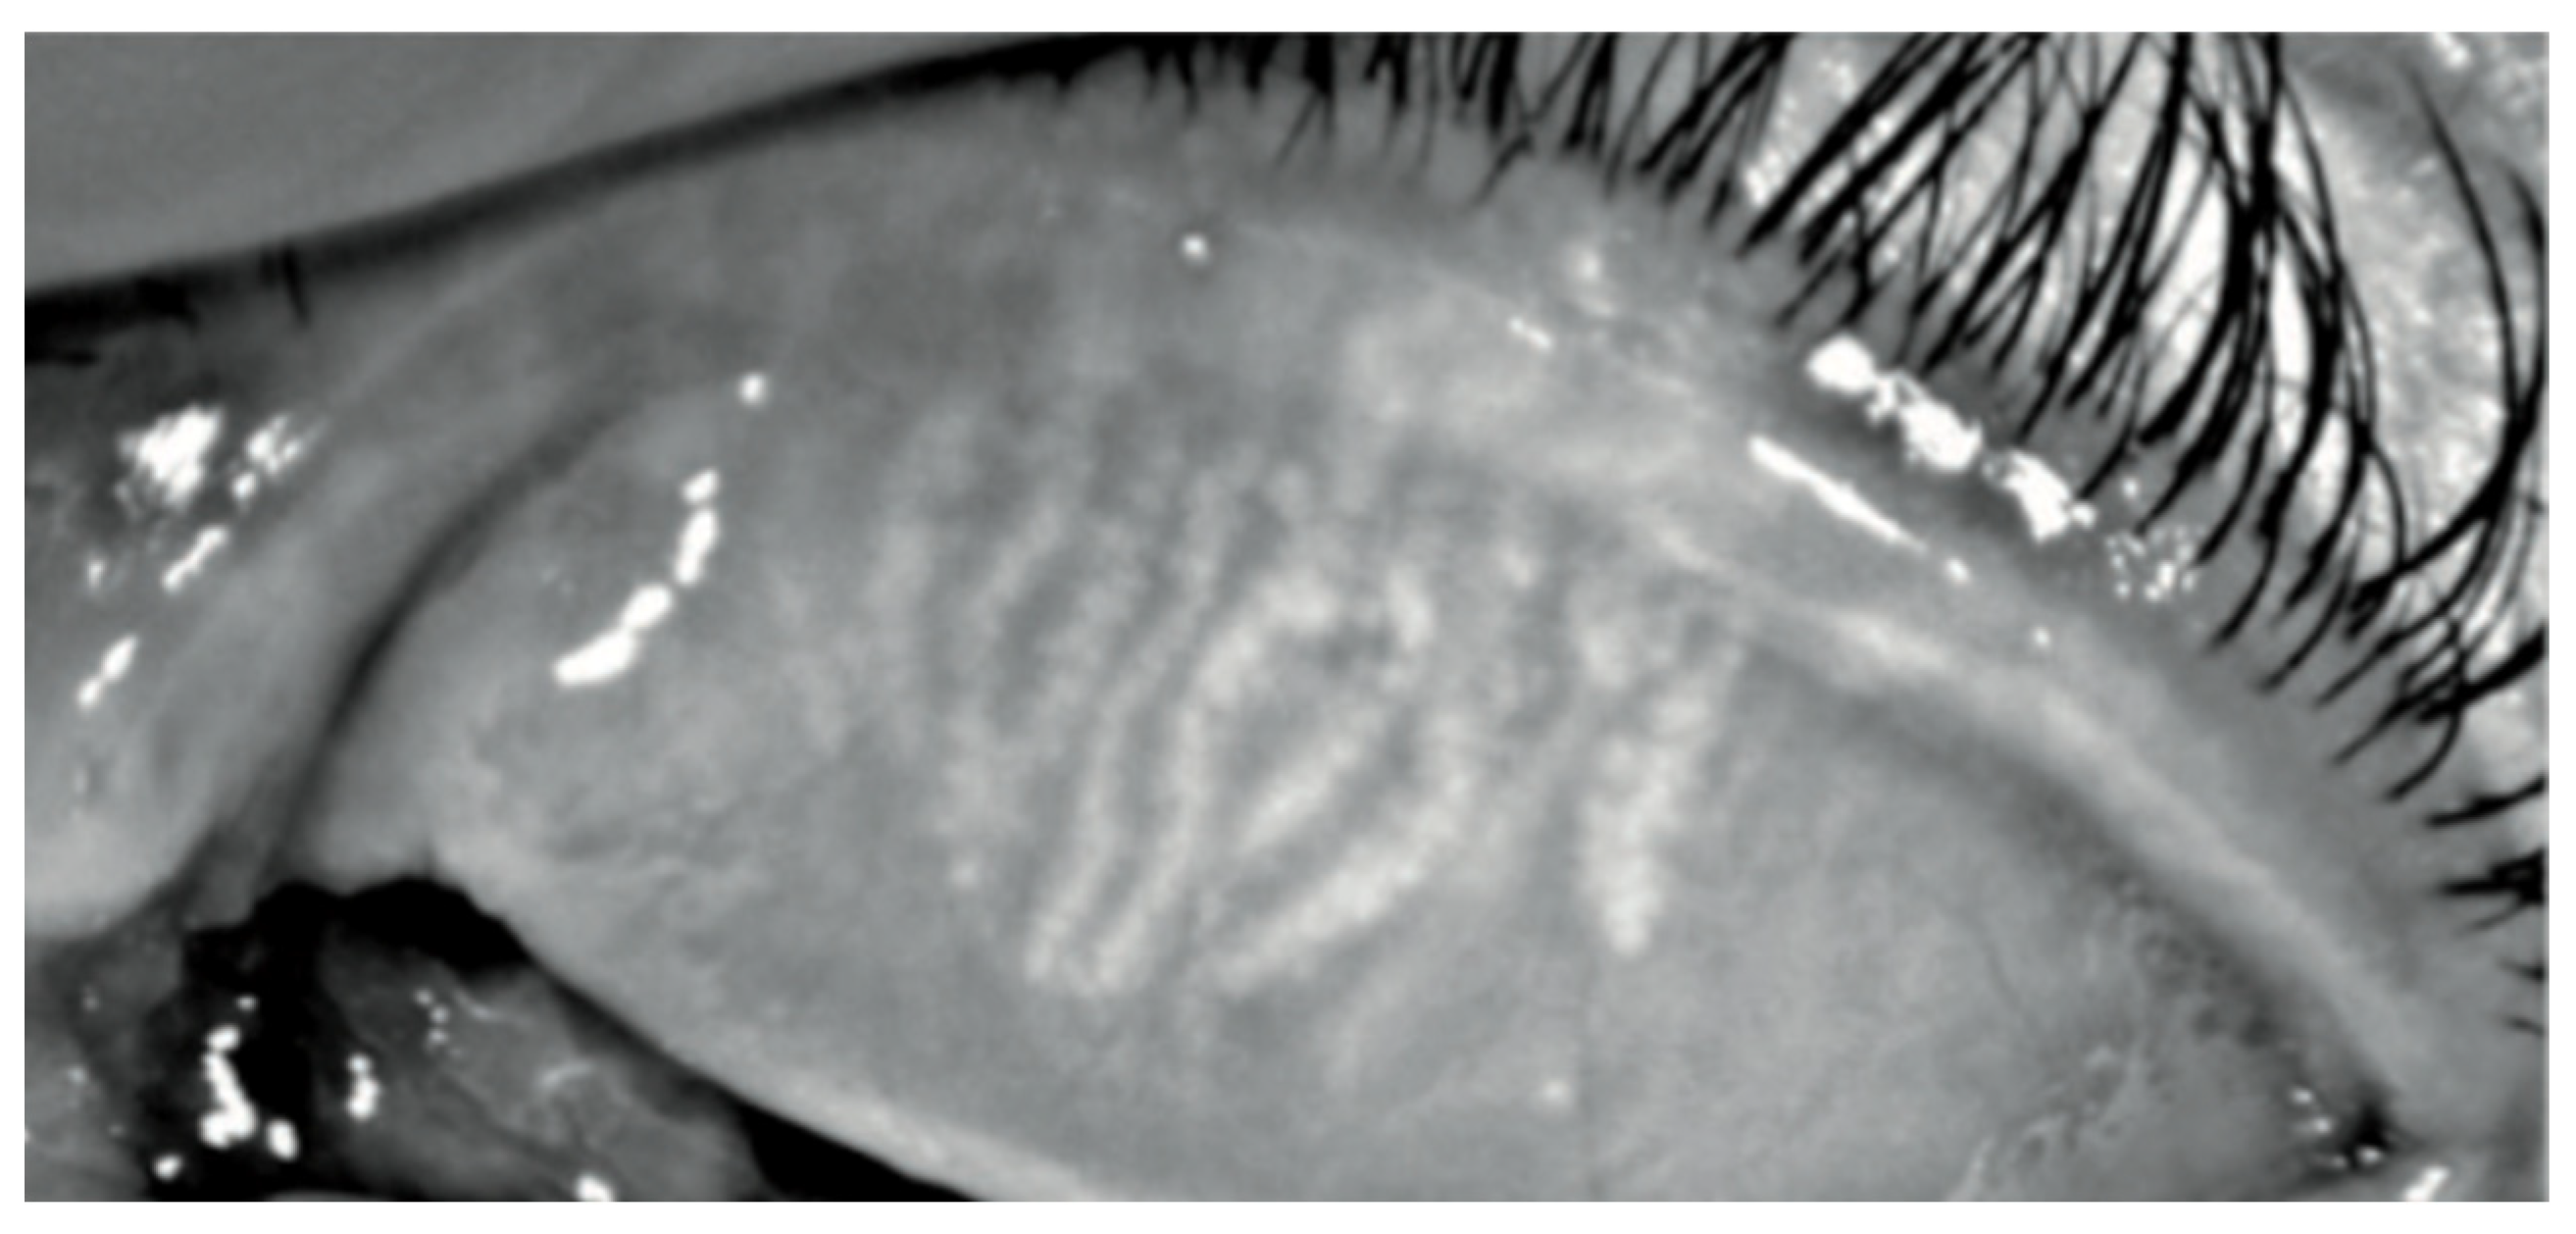

Among the naive group, three patients (27%) were symptomatic for ocular discomfort. In Group 2, sixteen patients (73%) presented with symptoms of ocular surface disease as itching or dry eye (Figure 1), but only seven patients of sixteen with symptoms (32%) reported worsening conditions after beginning Dupilumab injections (Table 3). No patients have developed sight-threatening complications, such as symblepharon and ocular surface keratinization. None discontinued the therapy because of the ocular side effects.

Figure 1. Color images of the eye in a case of Dupilumab-related conjunctivitis in Group 2: four quadrants of bulbar vessels are strongly dilated.